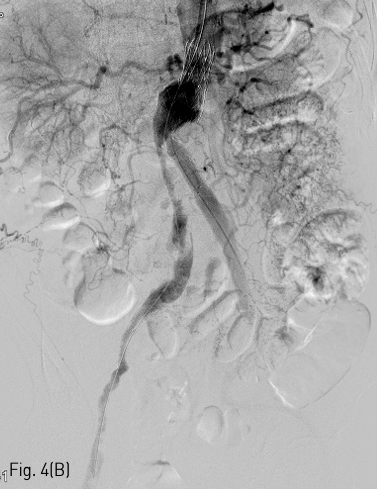

이후 우측 경로를 이용하여 AngioJet 기구를 진입시켜 2-3회에 걸쳐 혈전용해술을 시행하였고 우측 장골 분지의 내경은 회복되었다 (Fig. 4B). 이후 양측 경로에 들어있는 유도철사 (Terumo, Tokyo, Japan) 를 5Fr Berenstein catheter (Cordis, Milpitas, US) 를이용하여 Lunderquist (COOK medical, Søborg, Denmark) 유도철사로 교환한 뒤, Express LD premounted (Boston scientific, Boston, US) 스텐트를 우측은 8x37mm, 좌측은 10x37mm로 선택하여 꺽인 부위에 진입시켰다(Fig. 4C). 양측에서 조심스럽게 실시간으로 관찰하며 균형을 맞추어 스텐트를 설치하였다 (Fig. 4D). Mustang (Boston scientific, Boston, US) 9x60mm 크기의 풍선을 이용하여 설치 후 풍선확장술을 시행하여 최종적으로 스텐트의 모양을 완성하였다(Fig. 4E). 시술 직후 시행한 최종 혈관조영술 상에서 양측 분지로의 혈류가 정상적으로 회복되었으며, 혈류 속도도 양측이 균등함을 확인하였다(Fig. 5).

Fig 4B

(B) Abdominal aortography demonstrates successful re-canalization of right limb graft after thrombolysis treatment with AngioJet device.